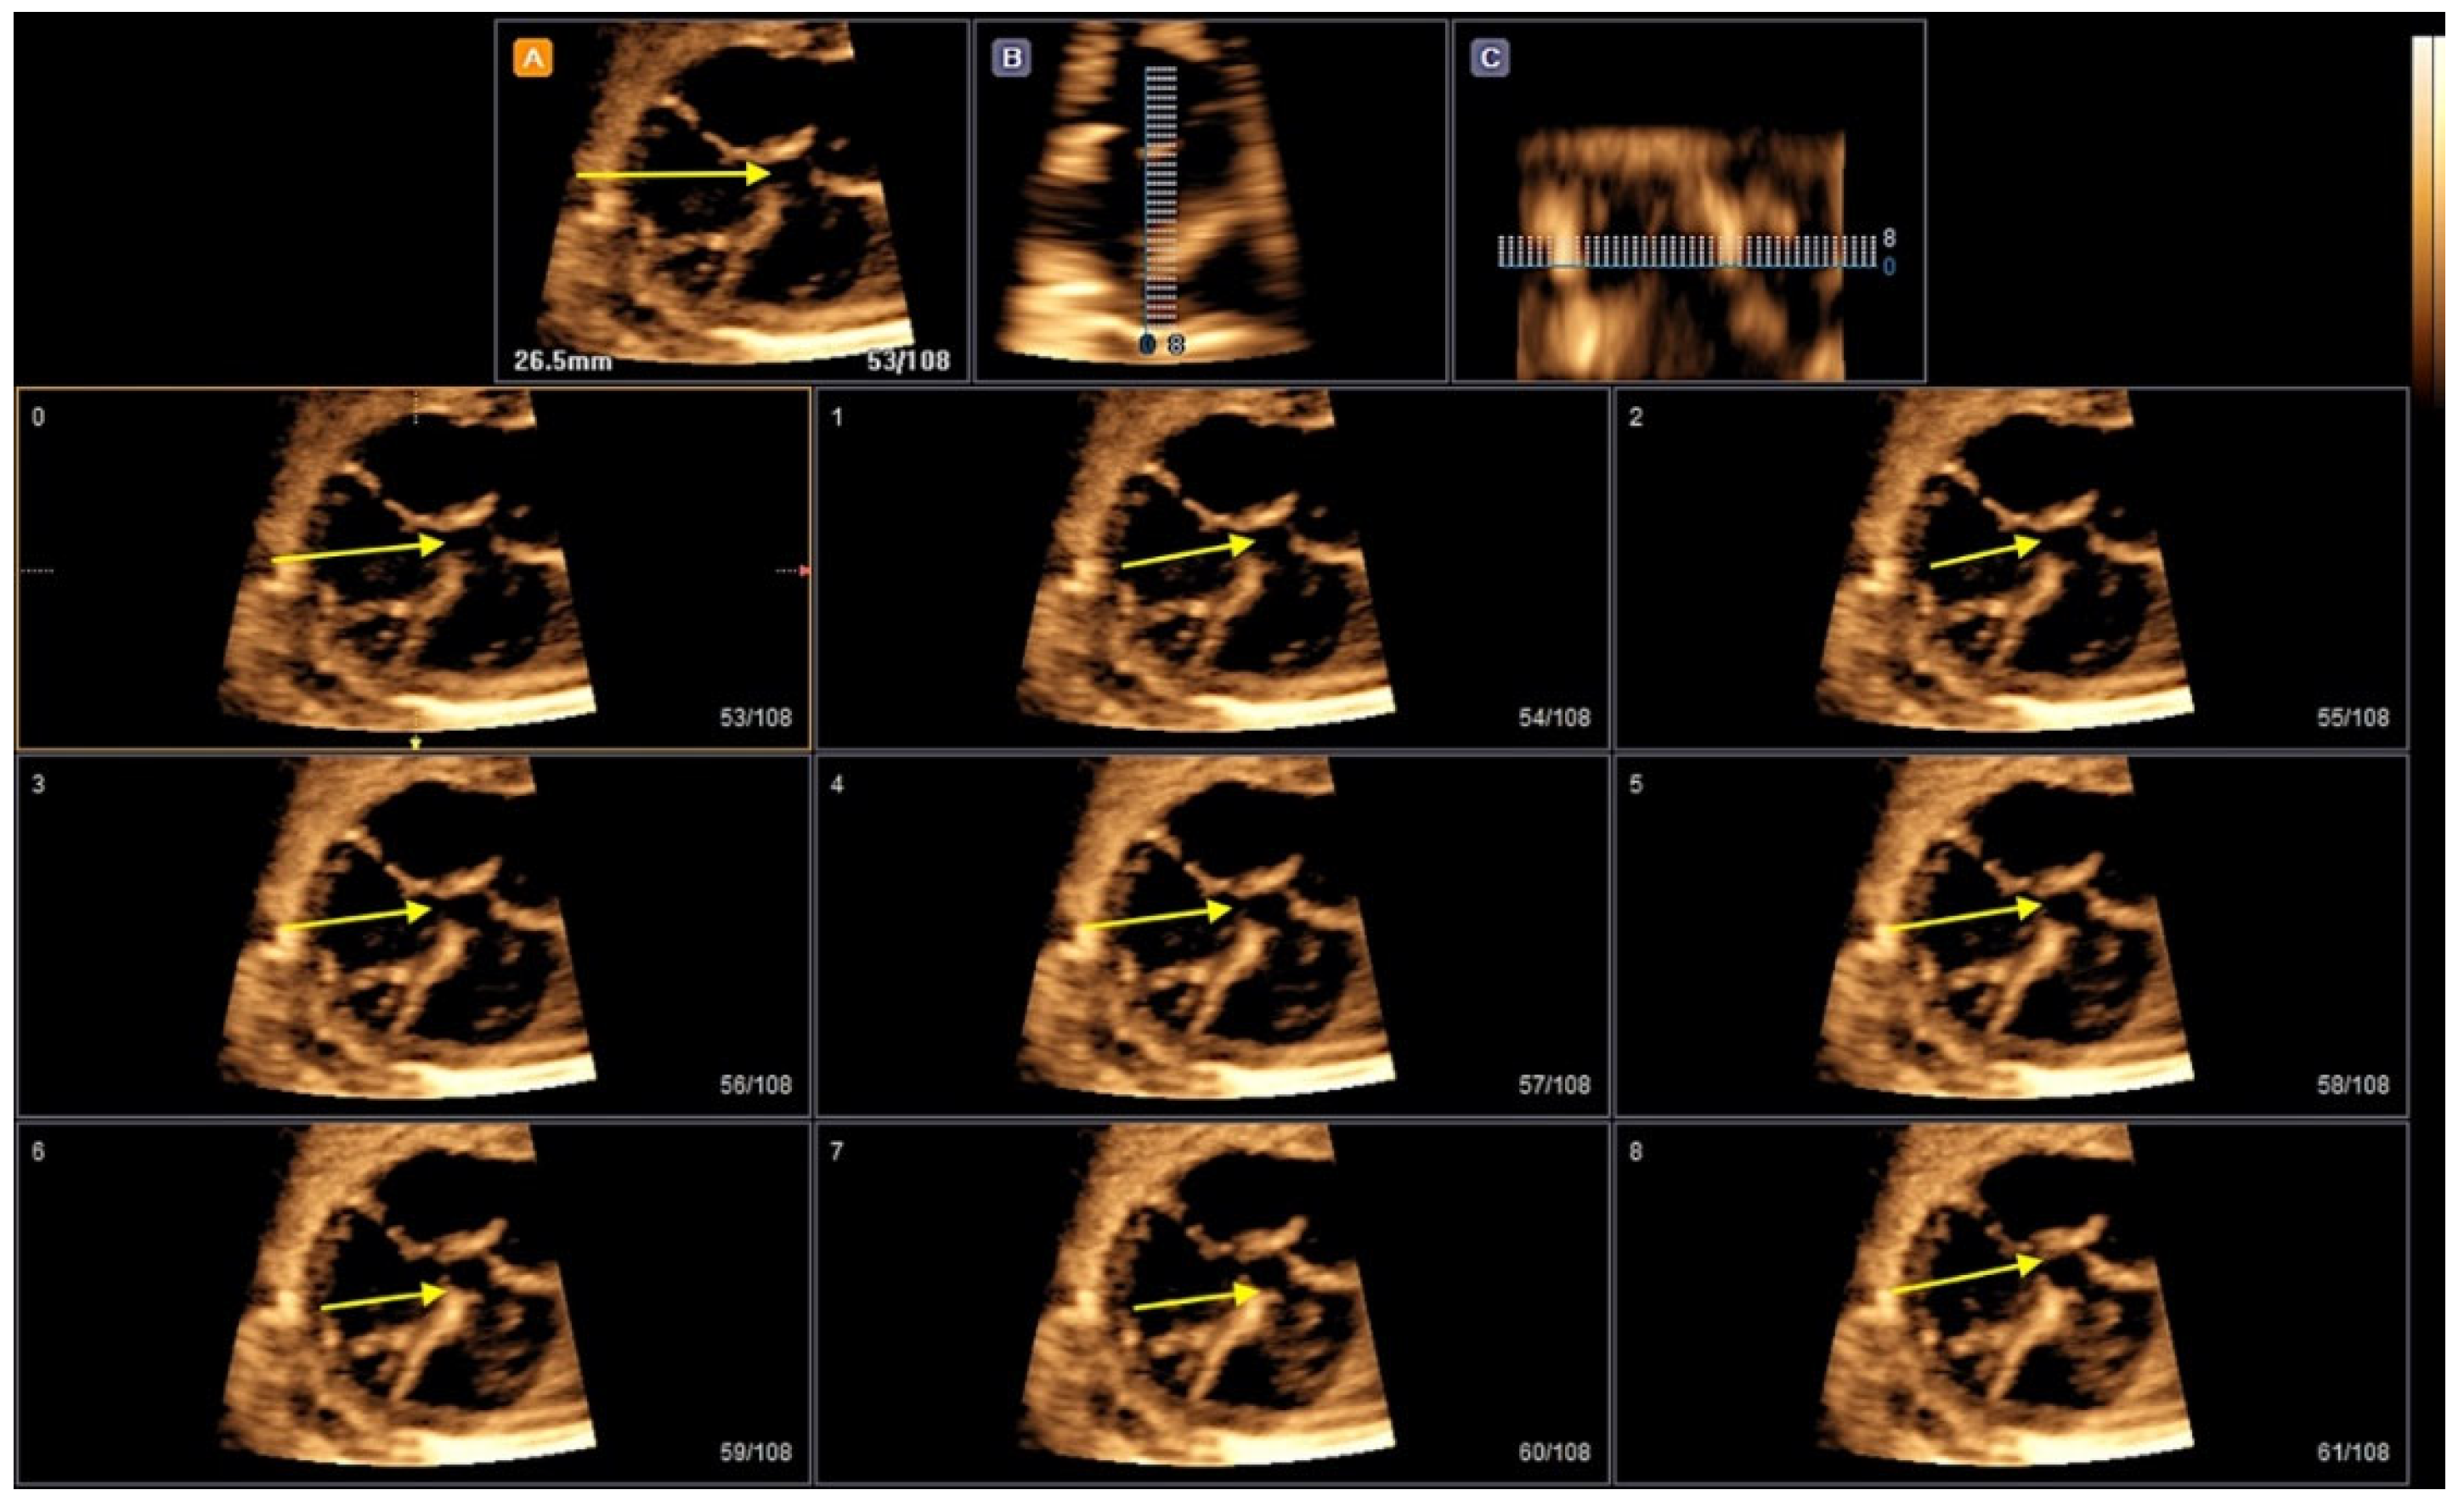

- Rizzo G, Capponi A, Vendola M, Pietrolucci ME, Arduini D. Role of tomographic ultrasound imaging with spatiotemporal image correlation for identifying fetal ventricular septal defects. J. Ultrasound Med. 2008, 27, 1071–1075.